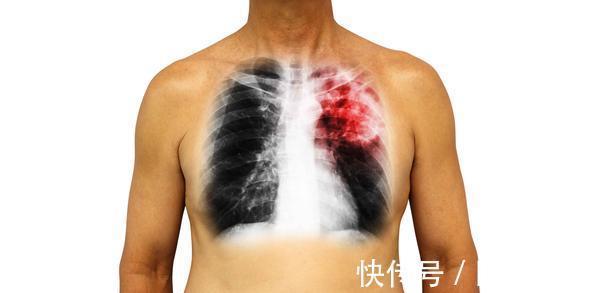

众所周知,当心梗疾病发生时,胸痛是典型的症状,所以在有了胸痛的表现后,很多人便先入为主的认为是心梗到来的信号,于是是便用治疗心梗的方式缓解病情,可是却没有达到理想的效果。

因为胸痛症状并不仅仅是心梗发病的症状,也有可能是肺栓塞到来了,尤其是下文中提到的5类人群,若是近期总是有胸痛表现,请赶紧到医院检查肺脏。

总的来说,肺栓塞是一种非常严重的疾病,一旦发生就有可能危及生命,所以也提醒大家必须给高度留意,尤其是以上5类人群,如果近期总是有胸痛的症状,很可能是肺栓塞到来的求救信号。这时请赶紧到医院做相关的检查,同时配合医生治疗。